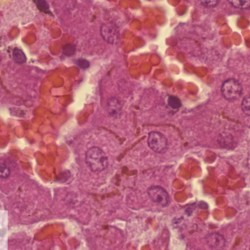

Etiquetes: N-811/01 2 total General Specie: General Organ: Liver Lesion: Cholestasis Lesion modifier: - Disease: - Files/Expedient: N-811/01 Not viewed General Specie: General Organ: Liver Lesion: Cholestasis Lesion modifier: - Disease: - Files/Expedient: N-811/01 Not viewed Títol Select...Avian (Exotic) (110)Avian (Poultry) (76)Bovine (317)Canine (935)Caprine (47)Equine (257)Feline (326)Ferret (19)General (127)Marine mammal (22)Non-human primate (20)Ovine (328)Porcine (379)Rabbit (61)Reptile (38)Rodent (28)Wildlife (91) Format Select...- (60)Abomasum (37)Adrenal gland (10)Blood (7)Blood vessel (50)Body as a whole (19)Bone (57)Bone marrow (21)Brain (93)Cloaca (1)Diaphragm (2)Ear (5)Esophagus (39)Eye (16)Fetus (12)Gallbladder (23)Gizzard (2)Heart (265)Intestine (356)Joint (32)Kidney (443)Larynx (5)Liver (326)Lung (264)Lymph node (91)Mammary gland (10)Mediastinum (1)Muscle (22)Nasal cavity (22)Nerve (7)Omasum (5)Oral cavity (63)Ovary (14)Oviduct (8)Pancreas (7)Parathyroid (5)Penis (10)Peritoneum (65)Pharynx (9)Pituitary gland (6)Placenta (7)Prostate (8)Proventriculus (3)Reticulum (1)Rumen (28)Sinus (7)Skin (181)Spinal cord (15)Spleen (105)Stomach (125)Teeth (1)Testicle (11)Thoracic cavity (31)Thymus (13)Thyroid gland (5)Tongue (32)Tonsils (11)Trachea (11)Urethra (5)Urinay bladder (61)Uterus (27)Vagina (1)Vulva (1)Yolk sac (1) Cobertura Select...- (152)Abomasitis (26)Abscess (27)Acidosis (1)Adenocarcinoma (20)Adenoma (9)Aerosacculitis (6)Agenesis (1)Agnathia (1)Alopecia (7)Amyloidosis (12)Aneurysm (6)Angiectasis (1)Anthracosis (1)Arteritis (11)Arthritis (15)Arthrogryposis (6)Artifact (4)Ascites (13)Atelectasis (8)Atherosclerosis (5)Atresia (1)Atrial septal defect (2)Atrophy (10)Autolysis (7)Bronchitis (6)Bronchopneumonia (26)Cachexia (2)Carcinoma (103)Cardiomyopathy (19)Cellulitis (2)Chemodectoma (4)Cholangiohepatitis (4)Cholangitis (19)Cholecystitis (4)Cholestasis (5)Chondrodysplasia (2)Chondrosarcoma (2)Chronic passive congestion (13)Chylothorax (2)Cirrhosis (6)Coelomitis (3)Coenurus cerebralis (4)Colitis (40)Congestion (17)Conjunctivitis (5)Coronitis (3)Cryptorchidism (3)Cyst (25)Cystitis (24)Dermatitis (69)Diaphragmatic hernia (4)Dilation (28)Discospondylitis (1)Disseminated intravascular coagulation (7)Dyschondroplasia (1)Dysplasia (29)Ectopia cordis (1)Ectopic ureter (1)Edema (55)Emphysema (5)Encephalitis (5)Endocardiosis (14)Endocarditis (26)Endometritis (5)Enteritis (118)Enterolith (6)Epulis (3)Esophagitis (14)Fasciitis (1)Fibrosis (7)Fibrous osteodystrophy (8)Fistula (1)Folliculitis (3)Fracture (2)Gastritis (34)Gingivitis (5)Glioma (8)Glomerulonephritis (21)Glossitis (25)Glycogenosis (1)Gout (8)Granuloma (2)Granulosa cell tumor (4)Hemangioma (9)Hemangiosarcoma (46)Hematoma (8)Hemoglobinuria (2)Hemopericardium (12)Hemoperitoneum (2)Hemorrhage (100)Hemosiderosis (7)Hemothorax (2)Hepatitis (78)Hernia (11)Histiocytosis (3)Hydatid cyst (11)Hydrocephalus (9)Hydrometra (1)Hydronephrosis (22)Hydropericardium (6)Hydrothorax (3)Hydroureter (5)Hyperkeratosis (8)Hyperostosis (4)Hyperplasia (37)Hypertrophy (9)Hypopigmentation (1)Hypoplasia (7)Hypopyon (1)Impaction (6)Infarction (63)Insulinoma (6)Intussusception (5)Jaundice (17)Laminitis (2)Laryngitis (2)Leiomyoma (5)Leukemia (13)Lipidosis (36)Lipoma (7)Lymphadenitis (45)Lymphadenopathy (7)Lymphangiectasia (6)Lymphangitis (5)Lymphoma (221)Malacia (11)Malignant melanoma (15)Mast cell tumor (11)Mastitis (8)Megaesophagus (2)Melanosis (3)Melena (4)Meningioma (6)Meningitis (6)Meningocele (2)Meningoencephalitis (5)Mesothelioma (5)Methemoglobinemia (2)Mineralization (10)Mucocele (5)Mucometra (1)Multilobular bone tumor (1)Mummification (3)Myelofibrosis (1)Myocarditis (4)Myositis (5)Necrosis (81)Nephritis (113)Nephroblastoma (6)Nephrosclerosis (1)Nephrosis (14)Neuritis (1)Obstruction (13)Omasitis (4)Omphalitis (1)Omphalophlebitis (7)Orchitis (4)Osteoarthrosis (5)Osteomyelitis (9)Otitis (2)Palatoschisis (3)Pancreatitis (3)Panniculitis (3)Papilloma (7)Parakeratosis (14)Patent ductus arteriosus (6)Peliosis hepatis (1)Perforation (17)Pericarditis (35)Peritonitis (39)Persistent right aortic arch (1)Pharyngitis (2)Pheochromocytoma (2)Phlebitis (2)Placentitis (6)Pleuritis (21)Pleuropneumonia (24)Pneumonia (109)Pneumothorax (3)Polycystosis (14)Polyp (5)Polyserositis (6)Posthitis (1)Proctitis (4)Prolapse (3)Prostatitis (3)Proventriculitis (1)Pyelonephritis (24)Pyometra (6)Pyothorax (4)Rhinitis (11)Rumenitis (6)Rupture (24)Salpingitis (3)Sarcoma (57)Sclerosis (1)Scoliosis (2)Seminoma (2)Sequestrum (2)Serous atrophy (14)Sinusitis (7)Splenitis (14)Splenomegaly (9)Spondylitis (6)Spondylosis (1)Stenosis (9)Stomatitis (32)Tenosynovitis (2)Teratoma (3)Thricobezoar (2)Thrombosis (16)Tonsilitis (4)Torsion (13)Tracheitis (4)Tympany (7)Typhlitis (8)Typhlocolitis (4)Ulcer (43)Urethritis (1)Urolithiasis (36)Uroperitoneum (1)Uveitis (1)Vasculitis (15)Ventricular septal defect (3)Volvulus (11) Matèria Select... - (14)- (1653)- (152)Abomasitis - Catarrhal (2)Abomasitis - Catarrhal-hemorrhagic (1)Abomasitis - Chronic (1)Abomasitis - Fibrinous-necrotizing (2)Abomasitis - Hyperplasic (5)Abomasitis - Hyperplasic - Chronic (1)Abomasitis - Necrotic (1)Abomasitis - Necrotizing (2)Abomasitis - Ulcerative (5)Adenocarcinoma (9)Aerosacculitis - Granulomatous (1)Amyloidosis - Chronic (1)Arteritis - Necrotic (2)Arteritis - Necrotizing (1)Arthritis - Chronic (4)Arthritis - Fibrinous-purulent (3)Arthritis - Serous (4)Arthritis - Subacute (1)Ascites - Serous (1)Atrophy - Serous (1)Bronchitis - Catarrhal (3)Bronchitis - Suppurative (1)Bronchopneumonia - Catarrhal-purulent (17)Bronchopneumonia - Fibrinous (1)Bronchopneumonia - Granulomatous (1)Bronchopneumonia - Purulent (1)Bronchopneumonia - Suppurative (5)Carcinoma - Adenocarcinoma (33)Carcinoma - Adenocarcinoma - Hepatocellular (2)Carcinoma - Adenocarcinoma - Mucinous (1)Carcinoma - Basosquamous (1)Carcinoma - Cholangiocellular (3)Carcinoma - Hepatocellular (4)Carcinoma - Metastatic (3)Carcinoma - Squamous cell carcinoma (13)Carcinoma - Transitional cell (2)Cardiomyopathy - Dilated (13)Cardiomyopathy - Hypertrophic (6)Cellulitis - Necrotizing (1)Cholangitis - Chronic (8)Cholangitis - Hyperplasic (3)Cholecystitis - Fibrinous-necrotizing (1)Coelomitis - Fibrinous (1)Coelomitis - Granulomatous (1)Colitis - Catarrhal (3)Colitis - Catarrhal-hemorrhagic (1)Colitis - Fibrinous (1)Colitis - Fibrinous-necrotizing (1)Colitis - Fibrinous-necrotizing (Diphtheritic) (6)Colitis - Granulomatous (2)Colitis - Hemorrhagic (4)Colitis - Hemorrhagic-necrotizing (3)Colitis - Necrotizing (2)Colitis - Ulcerative (6)Congestion - Chronic (2)Conjunctivitis - Hyperplasic (1)Conjunctivitis - Purulent (3)Coronitis - Ulcerative (1)Cystitis - Chronic (3)Cystitis - Fibrinous (1)Cystitis - Fibrinous-necrotizing (1)Cystitis - Follicular (1)Cystitis - Hemorrhagic (6)Cystitis - Hemorrhagic-ulcerative (1)Cystitis - Necrotizing (9)Cystitis - Perforated (1)Dermatitis - Granulomatous (14)Dermatitis - Hyperkeratotic (10)Dermatitis - Hyperplasic (proliferative) (1)Dermatitis - Hyperplastic (10)Dermatitis - Necrotizing (4)Dermatitis - Pustular (4)Dermatitis - Ulcerative (2)Dilation - Chronic (1)Discospondylitis - Necrotizing (1)Dysplasia - Follicular (5)Edema - Interstitial (6)Emphysema - Interstitial (1)Encephalitis - Granulomatous (1)Encephalitis - Nonsuppurative (1)Endocardiosis - Mitral (7)Endocardiosis - Mitral - Chronic (5)Endocarditis - Valvular (6)Endocarditis - Valvular - Mitral (7)Endocarditis - Valvular - Pulmonic (1)Endocarditis - Valvular - Subacute (1)Endocarditis - Valvular - Subaortic (5)Endocarditis - Valvular - Tricuspid (4)Endometritis - Purulent (3)Endometritis - Purulent-hemorrhagic (2)Enteritis - Catarrhal (23)Enteritis - Catarrhal - Acute (1)Enteritis - Catarrhal-hemorrhagic (5)Enteritis - Catarrhal-hemorrhagic - Acute (2)Enteritis - Fibrinous (16)Enteritis - Fibrinous - Acute (3)Enteritis - Fibrinous-necrotizing (7)Enteritis - Granulomatous (14)Enteritis - Granulomatous - Chronic (1)Enteritis - Granulomatous - Multifocal (1)Enteritis - Hemorrhagic (17)Enteritis - Hemorrhagic - Acute (1)Enteritis - Hemorrhagic-necrotizing (1)Enteritis - Hyperplasic (proliferative) (4)Enteritis - Necrotizing (4)Enteritis - Necrotizing - Acute (1)Enteritis - Necrotizing - Hemorrhagic (1)Enteritis - Necrotizing-ulcerative (2)Enteritis - Ulcerative (1)Enteritis - Ulcerative-hemorrhagic (1)Esophagitis - Erosive-ulcerative (6)Esophagitis - Necrotizing (4)Esophagitis - Ulcerative (1)Esophagitis - Ulcerative-necrotizing (1)Fasciitis - Fibrinous-purulent (1)Folliculitis - Purulent (2)Gastritis - Catarrhal (2)Gastritis - Chronic (1)Gastritis - Follicular (1)Gastritis - Hemorrhagic (2)Gastritis - Hemorrhagic-necrotizing (1)Gastritis - Hypertrophic (2)Gastritis - Inclusion bodies (1)Gastritis - Mineralization (1)Gastritis - Mycotic (1)Gastritis - Necrotizing (2)Gastritis - Ulcerative (6)Gastritis - Uremic (3)Gingivitis - Erosive (2)Gingivitis - Hyperplasic (proliferative) (1)Gingivitis - Necrotizing (1)Glomerulonephritis - Chronic (7)Glomerulonephritis - Membranoproliferative (3)Glomerulonephritis - Membranoproliferative - Chronic (1)Glomerulonephritis - Membranous (3)Glomerulonephritis - Membranous - Chronic (1)Glomerulonephritis - Proliferative (2)Glomerulonephritis - Subacute (1)Glossitis - Erosive (2)Glossitis - Granulomatous (6)Glossitis - Hyperplasic (1)Glossitis - Hyperplasic (proliferative) (2)Glossitis - Hyperplastic (1)Glossitis - Necrotizing (2)Glossitis - Necrotizing - Focal (1)Glossitis - Ulcerative (6)Glossitis - Ulcerative - Multifocal (1)Glossitis - Ulcerative - Subacute (1)Glycogenosis (1)Granuloma - Eosinophilic (1)Hemangiosarcoma - Metastatic (2)Hemorrhage - Acute (1)Hemorrhage - Subcapsular (3)Hepatitis - Abscess (9)Hepatitis - Acute (3)Hepatitis - Chronic (4)Hepatitis - Chronic interstitial (6)Hepatitis - Granulomatous (7)Hepatitis - Interstitial - Multifocal (1)Hepatitis - Interstitial - Subacute (1)Hepatitis - Necrotizing (17)Hepatitis - Necrotizing - Acute (2)Hepatitis - Necrotizing - Hemorrhagic (1)Hepatitis - Necrotizing - Subacute (1)Hepatitis - Pyogranulomatous (7)Hepatitis - Subacute (4)Hydronephrosis - Chronic (1)Hydropericardium - Chronic (1)Hyperplasia - Erythroid (1)Hyperplasia - Lymphoid (3)Hyperplasia - Myeloid (1)Hyperplasia - Nodular (8)Hypertrophy - Concentric (2)Hypertrophy - Eccentric (3)Infarction - Acute (17)Infarction - Acute - Multifocal (2)Infarction - Chronic (5)Infarction - Chronic - Multifocal (1)Infarction - Subacute (18)Infarction - Subacute - Focal (2)Laminitis - Chronic (2)Laryngitis - Necrotic (1)Laryngitis - Necrotizing (1)Leukemia - Lymphoid leukemia (2)Leukemia - Non-lymphoid leukemia (6)Lipidosis - Multifocal (1)Lipidosis - Panlobular (1)Lipidosis - Panlobular - Generalized (2)Lymphadenitis - Granulomatous (24)Lymphadenitis - Granulomatous - Chronic (3)Lymphadenitis - Hemorrhagic (1)Lymphadenitis - Necrotizing (5)Lymphadenitis - Necrotizing (caseous) (11)Lymphangitis - Granulomatous (1)Lymphangitis - Purulent (1)Lymphangitis - Ulcerative (1)Lymphoma - Alimentary lymphoma (7)Lymphoma - Cutaneous lymphoma (6)Lymphoma - Lymphosarcoma (2)Lymphoma - Mediastinal lymphoma (1)Lymphoma - Multicentric lymphoma (29)Malignant melanoma - Malignant (1)Malignant melanoma - Metastatic (1)Mast cell tumor - Metastatic (1)Mastitis - Fibrinous-purulent (2)Mastitis - Necrotic (1)Mastitis - Purulent (3)Mastitis - Suppurative (1)Meningitis - Fibrinous-purulent (2)Meningitis - Purulent (4)Meningoencephalitis - Necrotizing (3)Meningoencephalitis - Nonsuppurative (2)Mineralization - Metastatic (4)Myocarditis - Fibrous - Chronic (1)Myocarditis - Granulomatous (1)Myositis - Purulent (2)Necrosis - Acute (1)Necrosis - Cortical (5)Necrosis - Follicular (1)Necrosis - Papillary (8)Necrosis - Papillary - Acute (3)Necrosis - Subacute (3)Necrosis - Tubular (6)Nephritis - Embolic (2)Nephritis - Embolic suppurative (7)Nephritis - Granulomatous (27)Nephritis - Granulomatous - Chronic (1)Nephritis - Granulomatous - Multifocal (1)Nephritis - Interstitial (6)Nephritis - Interstitial - Acute (4)Nephritis - Interstitial - Chronic (41)Nephritis - Interstitial - Subacute (12)Nephritis - Purulent (7)Nephritis - Purulent - Acute (2)Nephritis - Purulent - Multifocal (3)Nephrosis - Cholemic (3)Nephrosis - Hemoglobinuric (10)Omasitis - Fibrinous-necrotizing (1)Omasitis - Hyperkeratotic (1)Omasitis - Necrotizing (2)Omphalophlebitis - Fibrinous-purulent (2)Omphalophlebitis - Purulent (3)Orchitis - Necrotizing (1)Osteomyelitis - Necrotizing (7)Osteomyelitis - Purulent (2)Otitis - Necrotizing (1)Otitis - Proliferative (1)Pancreatitis - Acute (1)Pancreatitis - Chronic (1)Pancreatitis - Granulomatous (1)Panniculitis - Fibrinous-purulent (1)Panniculitis - Necrotic (1)Panniculitis - Parasitic (1)Perforation - Acute (2)Pericarditis - Fibrinous (19)Pericarditis - Fibrinous - Subacute (1)Pericarditis - Fibrinous-necrotizing (1)Pericarditis - Fibrinous-purulent (3)Pericarditis - Fibrous (1)Pericarditis - Fibrous - Chronic (1)Pericarditis - Gangrenous (6)Pericarditis - Granulomatous (1)Pericarditis - Granulomatous - Chronic (2)Peritonitis - Acute (1)Peritonitis - Fibrinous (11)Peritonitis - Fibrinous - Subacute (1)Peritonitis - Fibrinous-purulent (5)Peritonitis - Fibrous (3)Peritonitis - Granulomatous (6)Peritonitis - Purulent (1)Peritonitis - Purulent-hemorrhagic (1)Peritonitis - Pyogranulomatous (3)Pharyngitis - Fibrinous-necrotizing (1)Pharyngitis - Ulcerative (1)Pheochromocytoma - Metastatic (1)Phlebitis - Purulent (1)Placentitis - Fibrinous-necrotizing (1)Placentitis - Necrotic (1)Placentitis - Necrotizing (1)Pleuritis - Chronic (1)Pleuritis - Fibrinous (3)Pleuritis - Fibrinous-purulent (2)Pleuritis - Fibrous (2)Pleuritis - Granulomatous (3)Pleuritis - Hyperplastic (2)Pleuritis - Purulent (2)Pleuritis - Pyogranulomatous (1)Pleuropneumonia - Fibrinous (13)Pleuropneumonia - Fibrinous-necrotizing (5)Pleuropneumonia - Granulomatous (2)Pleuropneumonia - Hemorrhagic-necrotizing (4)Pneumonia - Aspiration (11)Pneumonia - Bronchointerstitial (4)Pneumonia - Bronchointerstitial - Subacute (1)Pneumonia - Embolic (5)Pneumonia - Granulomatous (37)Pneumonia - Granulomatous - Multifocal (4)Pneumonia - Hemorrhagic-necrotizing (2)Pneumonia - Interstitial (7)Pneumonia - Interstitial - Acute (8)Pneumonia - Interstitial - Chronic (6)Pneumonia - Interstitial - Subacute (15)Pneumonia - Necrotizing (2)Pneumonia - Pyogranulomatous (2)Pneumonia - Verminous (5)Polyserositis - Fibrinous (6)Polyserositis - Fibrous (1)Proctitis - Fibrinous-necrotizing (1)Proctitis - Parasitic (2)Prostatitis - Purulent (1)Pyelonephritis - Acute (2)Pyelonephritis - Chronic (3)Rhinitis - Catarrhal (2)Rhinitis - Fibrinous (1)Rhinitis - Granulomatous (4)Rhinitis - Purulent (3)Rumenitis - Acute (1)Rumenitis - Erosive (1)Rumenitis - Necrotizing (1)Rupture - Acute (3)Sarcoma - Fibrosarcoma (12)Sarcoma - Hemangiosarcoma (11)Sarcoma - Histiocytic (7)Sarcoma - Metastatic (1)Sarcoma - Multilobular tumor of bone (1)Sequestrum - Chronic (2)Sinusitis - Suppurative (1)Splenitis - Granulomatous (8)Splenitis - Granulomatous - Chronic (1)Splenitis - Necrotizing (3)Splenitis - Necrotizing (caseous) (2)Spondylitis - Necrotizing (2)Stenosis - Intestinal (1)Stenosis - Valvular - Subaortic (4)Stomatitis - Erosive (12)Stomatitis - Erosive-ulcerative (3)Stomatitis - Fibrinous-necrotizing (1)Stomatitis - Fibrinous-necrotizing (Diphtheritic) (1)Stomatitis - Granulomatous (1)Stomatitis - Hyperplasic (1)Stomatitis - Hyperplasic (proliferative) (1)Stomatitis - Necrotizing (2)Stomatitis - Ulcerative (5)Stomatitis - Ulcerative - Multifocal (1)Stomatitis - Ulcerative-necrotizing (1)Tonsilitis - Necrotizing (4)Torsion - Acute passive hyperemia (5)Tracheitis - Catarrhal (3)Tracheitis - Fibrinous (1)Tracheitis - Granulomatous (1)Typhlitis - Catarrhal (1)Typhlitis - Fibrinous-necrotizing (2)Typhlitis - Hemorrhagic (2)Typhlitis - Ulcerative-hemorrhagic (1)Typhlocolitis - Fibrinous-necrotizing (2)Typhlocolitis - Proliferative (1)Ulcer - Chronic (6)Ulcer - Multifocal (2)Ulcer - Mycotic (1)Ulcer - Perforated (6)Urethritis - Hemorrhagic (1)Urolithiasis - Chronic (2)Uveitis - Granulomatous (1)Vasculitis - Granulomatous (1)Vasculitis - Necrotizing (1) Editor Select...- (1970)Acidosis (2)Actinobacillosis (Pleuropneumonia) (11)Aelurostrongylosis (2)African horse sickness (13)African swine fever (14)Alopecia X (1)Anaplasmosis (4)Anthrax (2)Aortic thromboembolism (feline) (7)Ascariasis (15)Aspergillosis (18)Atopic dermatitis (1)Atrophic rhinitis (3)Babesiosis (6)Blackhead (1)Bluetongue (11)Border disease (2)Bovine viral diarrhea (21)Brucellosis (2)Candidiasis (5)Canine distemper (14)Caprine arthritis-encephalitis (2)Capture myopathy (1)Cardiac insufficiency (17)Caseous lymphadenitis (7)Chlamydiosis (2)Classical swine fever (19)Clostridiosis (19)Coccidiosis (9)Coenurosis (4)Colibacillosis (21)Contagious ecthyma (7)Copper toxicosis (11)Cowdriosis (Heartwater) (3)Cryptococcosis (3)Cryptosporidiosis (2)Cysticercosis (23)Demodicosis (1)Diabetes (1)Dicrocoeliosis (5)Dictyocaulosis (4)Dirofilariasis (7)Discoid lupus erythematosus (3)Echinococcosis (17)Edema disease (7)Egg drop syndrome (1)Encephalitozoonosis (5)Enterotoxemia (1)Enzootic bovine leukosis (46)Epitheliogenesis imperfecta (3)Equine rhinopneumonitis (2)Equine verminous arteritis (strongylosis) (7)Erysipelas (5)Exudative epidermitis (7)Fasciolasis (11)Feline eosinophilic dermatoses (1)Feline hepatic lipidosis (8)Feline histiocytosis (4)Feline infectious peritonitis (38)Feline leukemia (4)Feline lower urinary tract disease (3)Feline panleukopenia (16)Feline viral rhinotracheitis (1)Flea allergy dermatitis (1)Foot and mouth disease (2)Gasterophilosis (4)Glasser's disease (15)Gousiekte (4)Gout (6)Haemonchosis (9)Hemolytic anemia (4)Hemorrhagic diathesis (1)Hepatic insufficiency (11)Hepatosis dietetica (7)Herpesvirosis (6)Hyperadrenocorticism (7)Hyperparathyroidism (10)Hypertrophic osteopathy (6)Hypervitaminosis D (1)Hypodermosis (1)Inclusion body hepatitis (4)Infectious bovine rhinotracheitis (5)Infectious bronchitis (5)Infectious canine hepatitis (13)Influenza (4)Juvenile nephropathy (8)Lamb dysentery (4)Leishmaniasis (28)Leptospirosis (1)Leukosis (5)Listeriosis (4)Lumpy skin disease (3)Maedi-visna (4)Malignant catarrhal fever (12)Mange (6)Mannheimiosis (5)Marek's disease (7)Metabolic bone disease (2)Mucoid enteropathy (5)Mulberry heart disease (5)Myasis (1)Mycobacteriosis (22)Mycosis fungoides (6)Myxomatosis (3)Necrobacillosis (5)Neonatal isoerythrolysis (6)Nocardiosis (4)Oestrosis (2)Onchocerciasis (1)Osteochondrosis (1)Ostertagiosis (6)Ovine pulmonary adenocarcinoma (5)Oxyuriasis (1)Pacheco's disease (4)Papillomatosis (6)Paratuberculosis (18)Parvovirosis (17)Pasteurellosis (11)Pemphigus foliaceus (1)Periodontal disease (1)Polioencephalomalacia of ruminants (4)Polyarteritis nodosa (3)Polycystic kidney disease (13)Porcine circovirosis (11)Porcine dermatitis and nephropathy syndrome (9)Porcine proliferative enteropathy (4)Porcine reproductive and respiratory syndrome (6)Porcine stress syndrome (1)Pox (13)Pregnancy toxemia (3)Proventricular dilatation disease (2)Pseudotuberculosis (yersiniosis) (2)Psittacine beak and feather disease (PBFD) (5)Pyoderma (4)Q fever (4)Rabbit hemorrhagic disease (2)Renal insufficiency (12)Reticuloendotheliosis (2)Rhodococcosis (1)Rickets (1)Rinderpest (2)Salmonellosis (34)Sarcosporidiosis (2)Schmallenberg (7)Septicemia (23)Spirocercosis (11)Streptococcosis (5)Strongylosis (1)Swine dysentery (5)Systemic coronavirosis (5)Tetralogy of Fallot (5)Theileriosis (13)Thromboembolism (5)Toxoplasmosis (11)Transmissible viral proventriculitis (1)Traumatic reticuloperitonitis (3)Traumatism (16)Tuberculosis (58)Ulcerative lymphangitis (1)Uremic syndrome (20)Viral arthritis (6)White muscle disease (9)Wobbler syndrome (2)Xanthomatosis (1)Zygomycosis (4) Idioma Select...- (1180)Bacterial (501)Degeneration (106)Fungal (46)Hemodynamic (112)Idiopathic (22)Inflammation (58)Malformation (88)Neoplasia (343)Nutritional (41)Parasitic (243)Physical/Chemical (93)Toxic (44)Viral (304) Ítem destacat Porcine Sow. Porcine Ulcerative Dermatitis Syndrome (PUDS). Interface dermatitis. Lesions were neither painful nor pruritic. University of Pretoria, South…